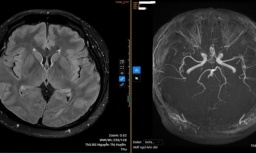

Hà Nội thí điểm trí tuệ nhân tạo tại 3 bệnh viện để phát hiện sớm ung thư, đột quỵ -